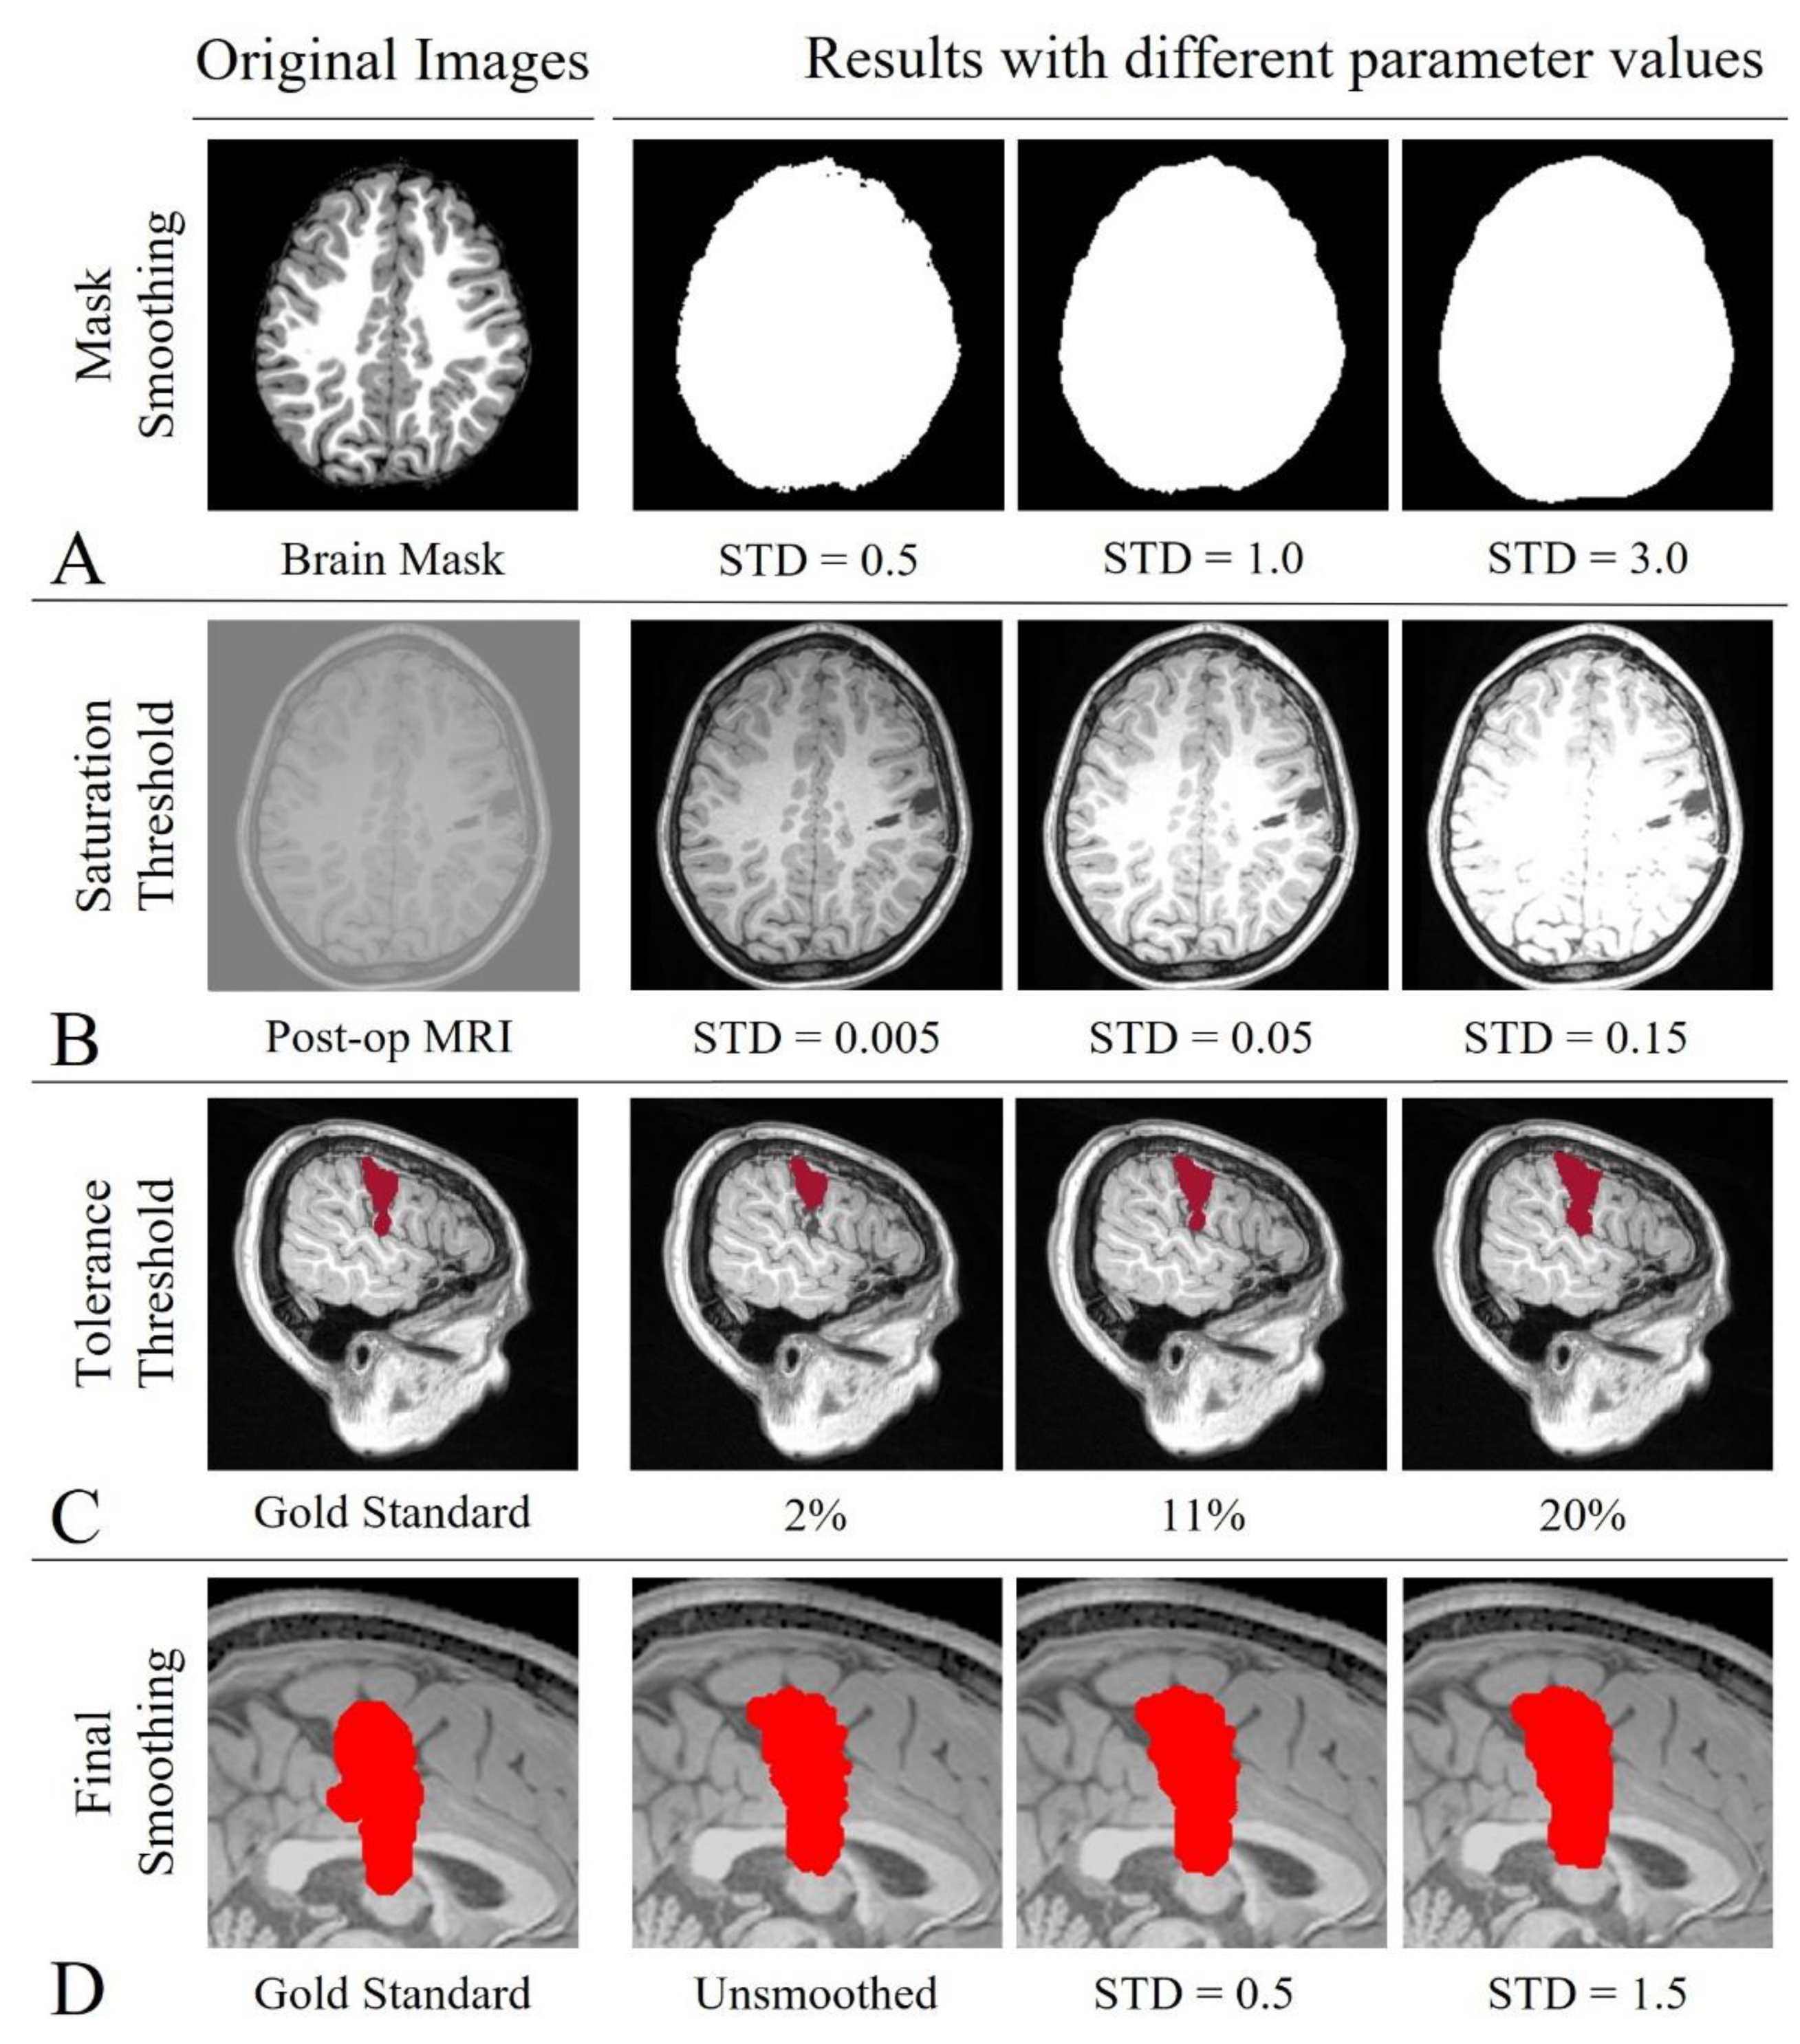

3.4. Single-Parameter Tuning

| Parameter | Applied to | Tested Values | Standardization | |

|---|---|---|---|---|

| ADJ-G ADJ-L | NORM-G NORM-L | |||

| Smoothing | Brain Mask | 0.5; 1; 3 | 3 Values | |

| Tolerance Threshold | Region-Growing | 2%; 5%; 8%; 11%; 14%; 17%; 20% | 7 Values | |

| Saturation Threshold | Post-op MRI | 0.1%; 0.5%; 1%; 5%; 10%; 15% | 6 Values | n/a |

| Smoothing | Output | 0.1; 0.5; 1; 1.5 | 4 Values | |

| Total Number of Combinations (Segmentation Pipelines) | 504 | 84 | ||

| Parameter | ADJ-G | ADJ-L | NORM-G | NORM-L |

| Mask Smoothing | 0.5 | 0.5 | 0.5 | 0.5 |

| Tolerance Threshold | 0.05 | 0.05 | 0.02 | 0.02 |

| Final Smoothing | 0.5 | 0.5 | 0.1 | 0.5 |

| Saturation Threshold | 10% | 10% | NA | NA |

| DSC Median (IQR) | 0.76 (0.68–0.85) | 0.83 (0.72–0.85) | 0.78 (0.68–0.83) | 0.79 (0.66–0.86) |